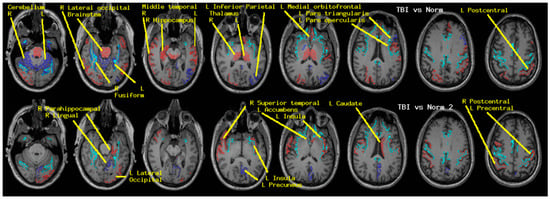

Regional measures of neuroelectric activity for 17 subcortical and 68 cortical regions were combined into classifiers using stepwise linear classification [16]. Classification accuracies with p-values are shown in Table 5. The cortical and subcortical regions which contributed to the classifier in order of their statistical contribution were R thalamus, R cerebellum, R middletemporal, R hippocampus, R lateraloccipital, L isthmuscingulate, L thalamus, L fusiform, brain-stem, and 11 others. When these 20 regions were excluded, classification accuracy remained highly significant albeit reduced. The contributing regions in order were L insula, L lingual, R superior temporal, L caudate, L parahippocampal, and seven others.

As for the cortical and subcortical regions, regional measures of neuroelectric activity for 18 deep white matter tracts were combined into classifiers. Classification accuracies with p-values are shown in Table 5. The regions which contributed to the classifier in order were left cortico-spinal tract (L_cst), right inferior longitudinal fasciculus (R_ilf), R_cst, forceps minor (fminor), and six others.

Discriminant analysis reduces all of the measures for an individual to a single score for each classifier. Here, each individual has two scores, one for the cortical/subcortical classifier and one for the deep white matter tract classifier. Figure 2 shows these scores in bivariate plots to illustrate the “spatial” separation which results in the classification accuracies shown in Table 5 (Figure 3).

The components of each classifier are the measures for each included region. The discriminant analysis algorithm identifies those regions for which there are differences between the cohorts and constructs a linear combination of those regions’ measures which adds the differences to enable significant separation/classification.

Figure 4 illustrates the differences for each subcortical region. A dot is plotted for each subject of the CamCAN cohort (upper panel) and the TEAM-TBI cohort (lower panel). Since each measure is a z-score computed from the mean and standard deviation for that region from the CamCAN cohort, the plots for the CamCAN cohort all have a mean of 0.0, standard deviation of 1.0, and are nearly symmetrically distributed about the mean.

Lack of symmetry primarily results from the fact that each measure has a floor since each measure is a normalized count. The floor for each region is indicated in the figure with a horizontal bar. No individual’s measure for a region can fall below that bar; this results in bunching of the values below the mean. This is most pronounced for the accumbens regions for which the floor is only slightly more than one standard deviation below the mean.

The regions whose contributions to the classifier were greatest are listed above and in Figure 4 (subcortical) and Figure 5 (right cortical). The means for each of those regions is markedly displaced from 0.0 as expected.

6.1. Potential Clinical Utility

This study was undertaken to utilize and assess MEG-derived measures for the diagnosis and monitoring of treatment for chronic symptoms of TBI. We report results which demonstrate (a) sensitivity to the presence/absence of insomnia, somatization, depression, and anxiety (Table 1 and Table 3, Figure 1) and (b) sensitivity to history of concussion and/or chronic symptoms (Table 5, Figure 2, Figure 3, Figure 4 and Figure 5). We cannot directly tie these MEG results to TBI. However, for clinical purposes, the etiology may not matter so long as we can use the measures to more effectively diagnose and treat.